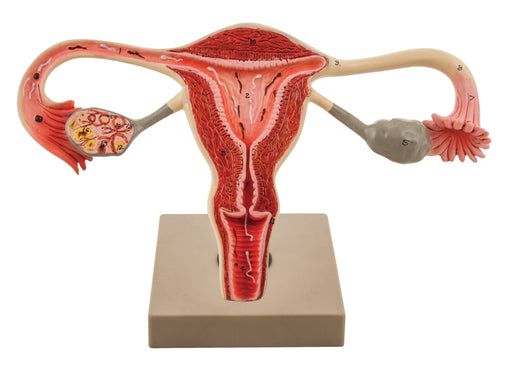

Model, Human, Female Reproductive, Ovary

3 x life size 12" x 5.5" x 8" Internal structure of human female reporductive system displayed in aproximently 3 times life size. Shows Vagina, ...

Eisco 3x Life-Size Human Female Reproductive System, Cross Section

Enlarged approx. 3 times. Enlarged approx. 3 times. This model represent the frontal section through female genital organ. Mounted on base. Numbere...